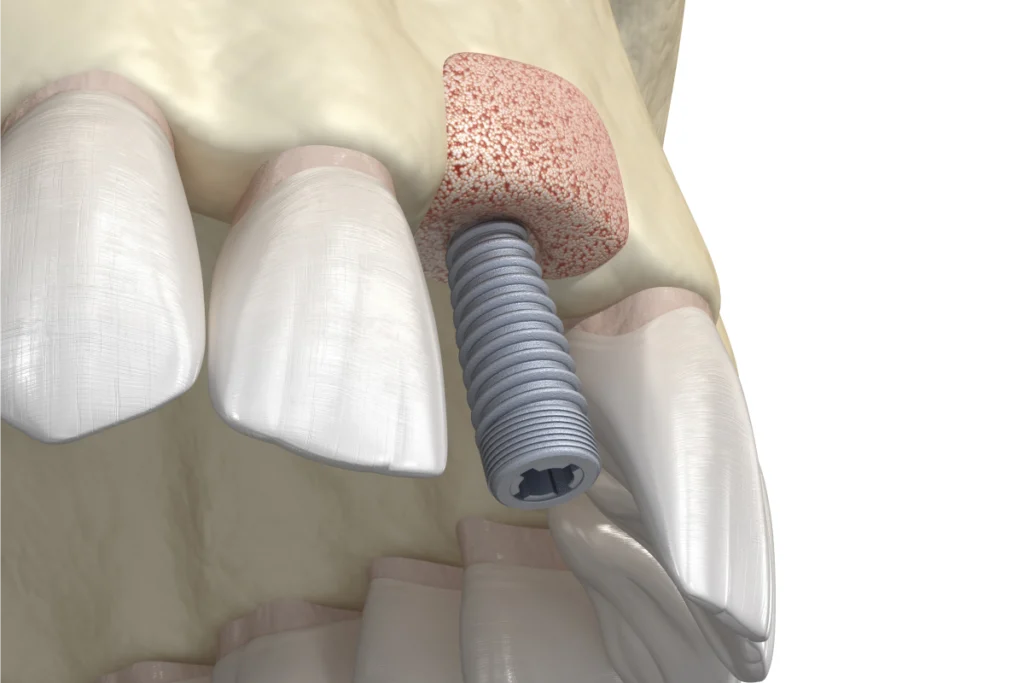

La greffe osseuse est souvent nécessaire avant la pose d’un implant dentaire, en particulier chez les patients ayant subi une perte osseuse importante. Elle consiste à prélever de l’os au niveau du menton, de la mâchoire ou d’une zone donneuse pour l’intégrer au site receveur. Le dentiste peut également utiliser des matériaux synthétiques ou des biomatériaux pour augmenter le volume osseux.

Cette intervention permet de recréer une base solide pour l’implant et améliore la stabilité de la future prothèse. Après la greffe, une période de cicatrisation de plusieurs mois est généralement nécessaire pour permettre l’intégration de l’os.

Chirurgie pré-implantaire

La chirurgie pré-implantaire prépare la mâchoire à recevoir des implants dentaires en corrigeant les défauts osseux ou les irrégularités gingivales. Le dentiste peut réaliser un comblement de sinus (sinus lift) pour augmenter la hauteur osseuse dans la région postérieure de la mâchoire supérieure. Il peut également effectuer une régénération osseuse pour renforcer la zone de pose de l’implant. En outre, il peut remodeler les tissus mous pour garantir une meilleure esthétique autour des implants. Ces interventions augmentent la stabilité de l’implant et assurent un résultat fonctionnel et esthétique durable.

Les implants dentaires sont-ils possibles après une extraction ?

Oui, nous pouvons poser un implant dentaire après une extraction. Dans certains cas, nous réalisons toutefois une greffe osseuse afin de garantir une base suffisamment solide pour accueillir l’implant.